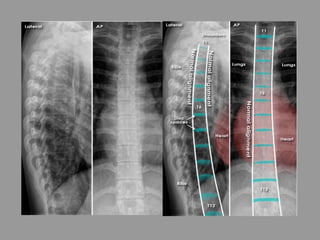

Thoracolumbar spine - Systematic approach

• Lateral and AP

• Coverage - The whole spine is visible on both views

• Alignment - Follow the corners of the vertebral bodies from one

level to the next

• Bones - The vertebral bodies should gradually increase in size

• Spacing - Disc spaces gradually increase from

superior to inferior - Note: Due to magnification

and spine curvature the vertebral bodies and discs

at the edges of the image can appear larger than

those in the centre of the image

• Soft tissues - Check the paravertebral line (see AP

image below)

• Edge of image - Check the other structures visible

Thoracic spine - Systematic approach

• Alignment - Vertebral body alignment is

assessed by carefully matching the anterior

and posterior corners of the vertebral bodies

with the adjacent vertebra

• Bones - Gradual increase in vertebral body

height from superior to inferior

• Spacing - Disc spaces gradually increase in

VB = Vertebral body

P = Pedicle

SP = Spinous process (ribs overlying)

F = Spinal nerve exit foramen

• Alignment - The vertebral bodies and spinous processes

(SP) are aligned

• Bones - The vertebral bodies and pedicles are intact

• Other visible bony structures include the transverse

processes (TP), ribs, and the costovertebral and

costotransverse joints

• Spacing - Each disc space is of equal height when

comparing left with right. The pedicles gradually become

wider apart from superior to inferior

• Soft tissue - Note the normal paravertebral soft tissue

which forms a straight line on the left - distinct from the

aorta